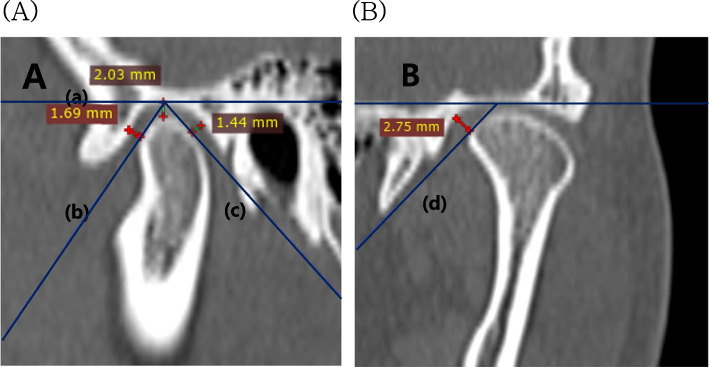

Methods: The study included 16 patients (6 with Class II malocclusion, 10 with Class III malocclusion) who underwent bilateral sagittal split ramus osteotomy at Chonnam National University Hospital. Cone-beam CT data were collected at three specific time points: before surgery, immediately after surgery, and approximately 6 months post-surgery. Mandibular movement was measured using InVivoDental 5.4.6. ITK-SNAP 3.8.0 was used to assessed condylar volume changes post-surgery. Condyle positions were evaluated in four parts with RadiAnt DICOM Viewer 4.6.9. Statistical analyses were performed using the SPSS version 23.

Results: Considering both Class II and III malocclusion, a 2.91% volume reduction was noted immediately and at 6 months after surgery. Both Class II and III cases demonstrated a decrease in superior joint space by -0.59 mm and medial joint space by -1.09 mm. No significant correlation was found between this process and condylar volume change.